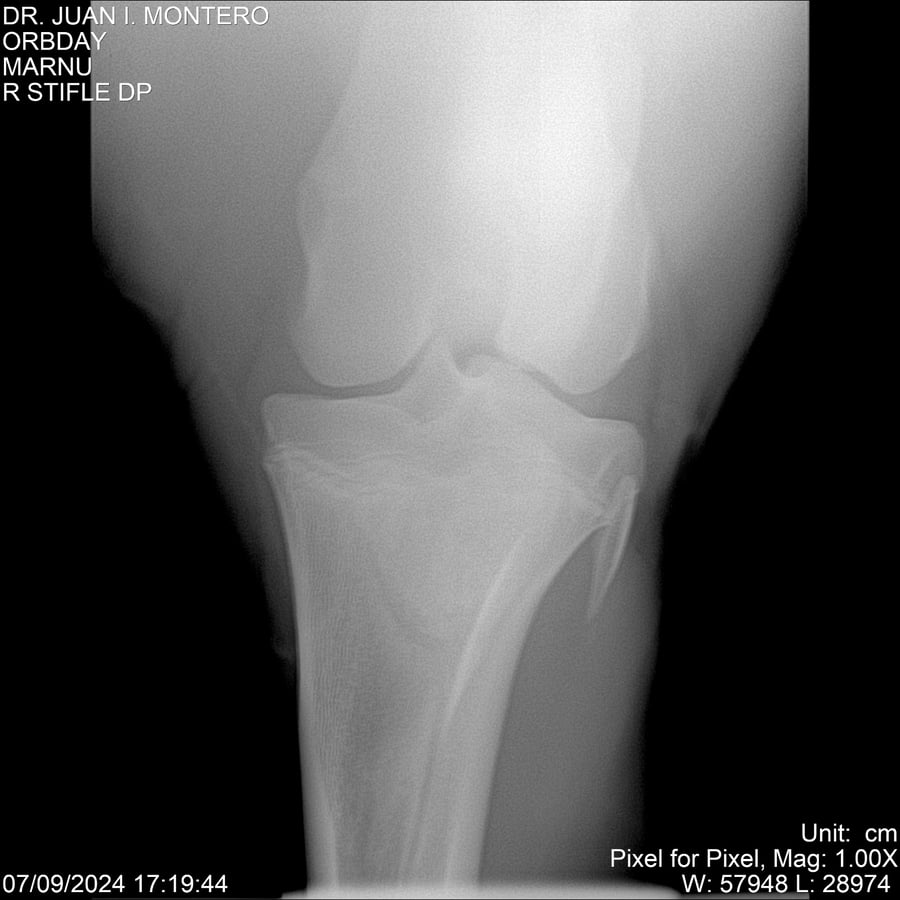

• Empresa: Abelenda N. R., Walter Hugo